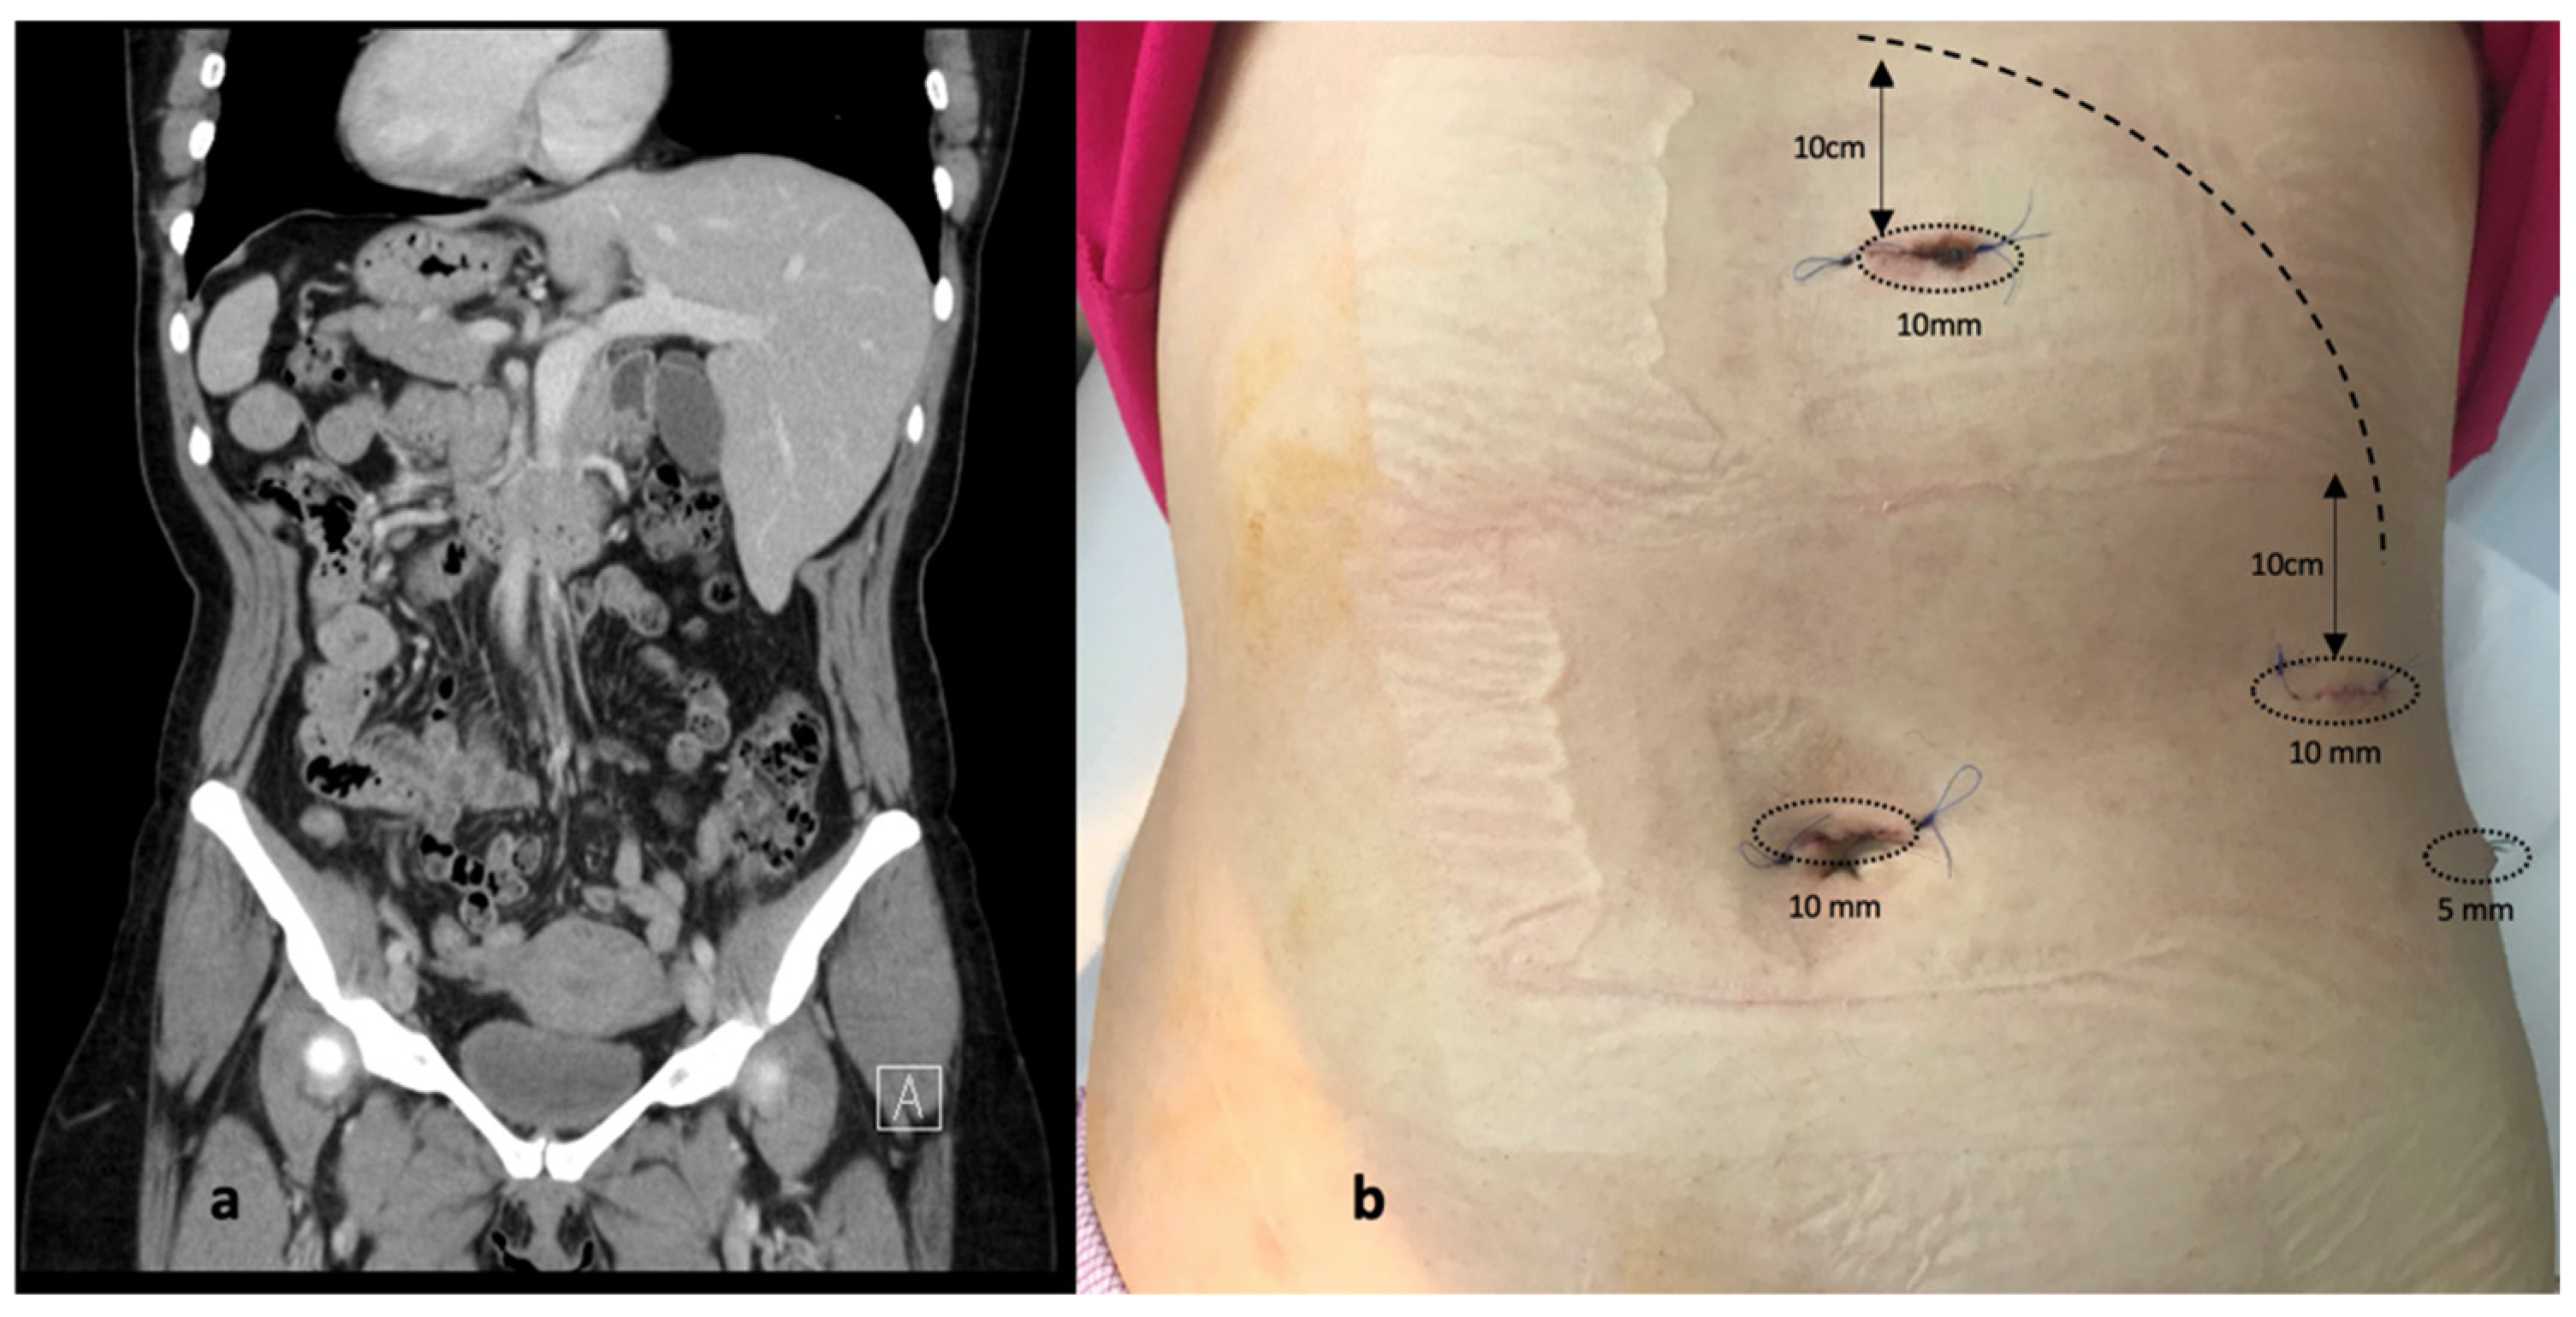

3.1. Case Report